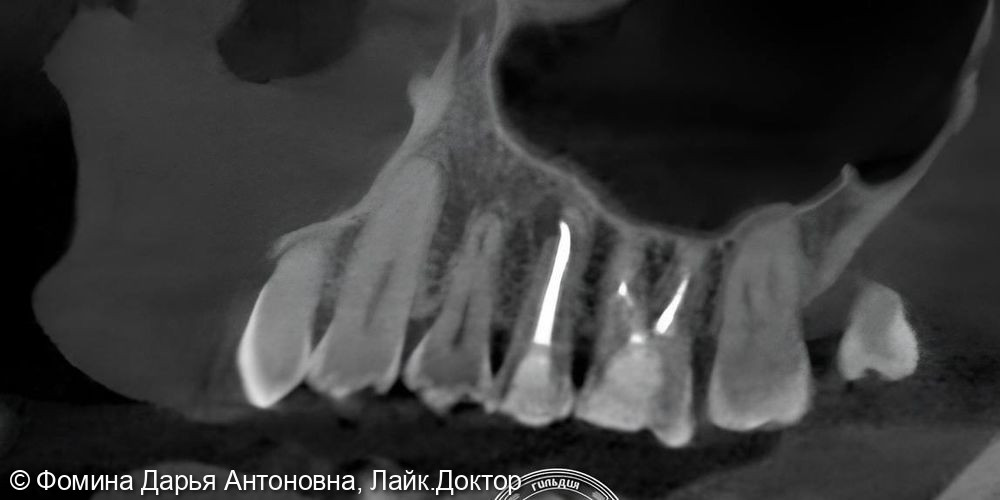

Зуб был пролечен около 5 лет назад в другой клинике и клинически не беспокоил. Однако при проведении КЛКТ выявили периапикальный очаг воспаления — скрытую инфекцию у верхушки корня.

Диагностика с помощью 3D-КТ: источник боли был обнаружен в 16 зубе – воспаление на верхушках корней. Зуб ранее лечили от кариеса более 5 лет назад.